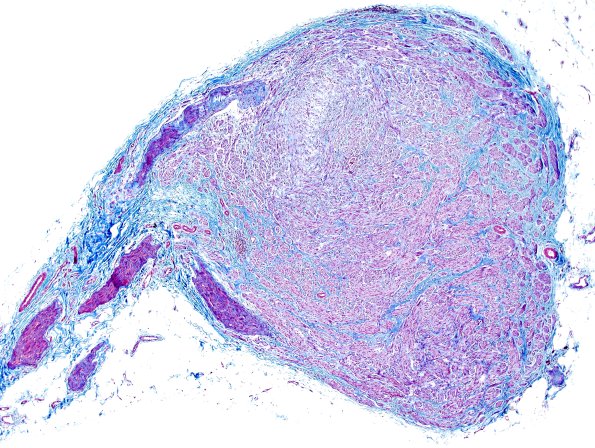

1E1 Neuroma, traumatic (Case 1) Trichrome-1

A trichrome stain highlights the admixed fibrosis. (Trichrome)